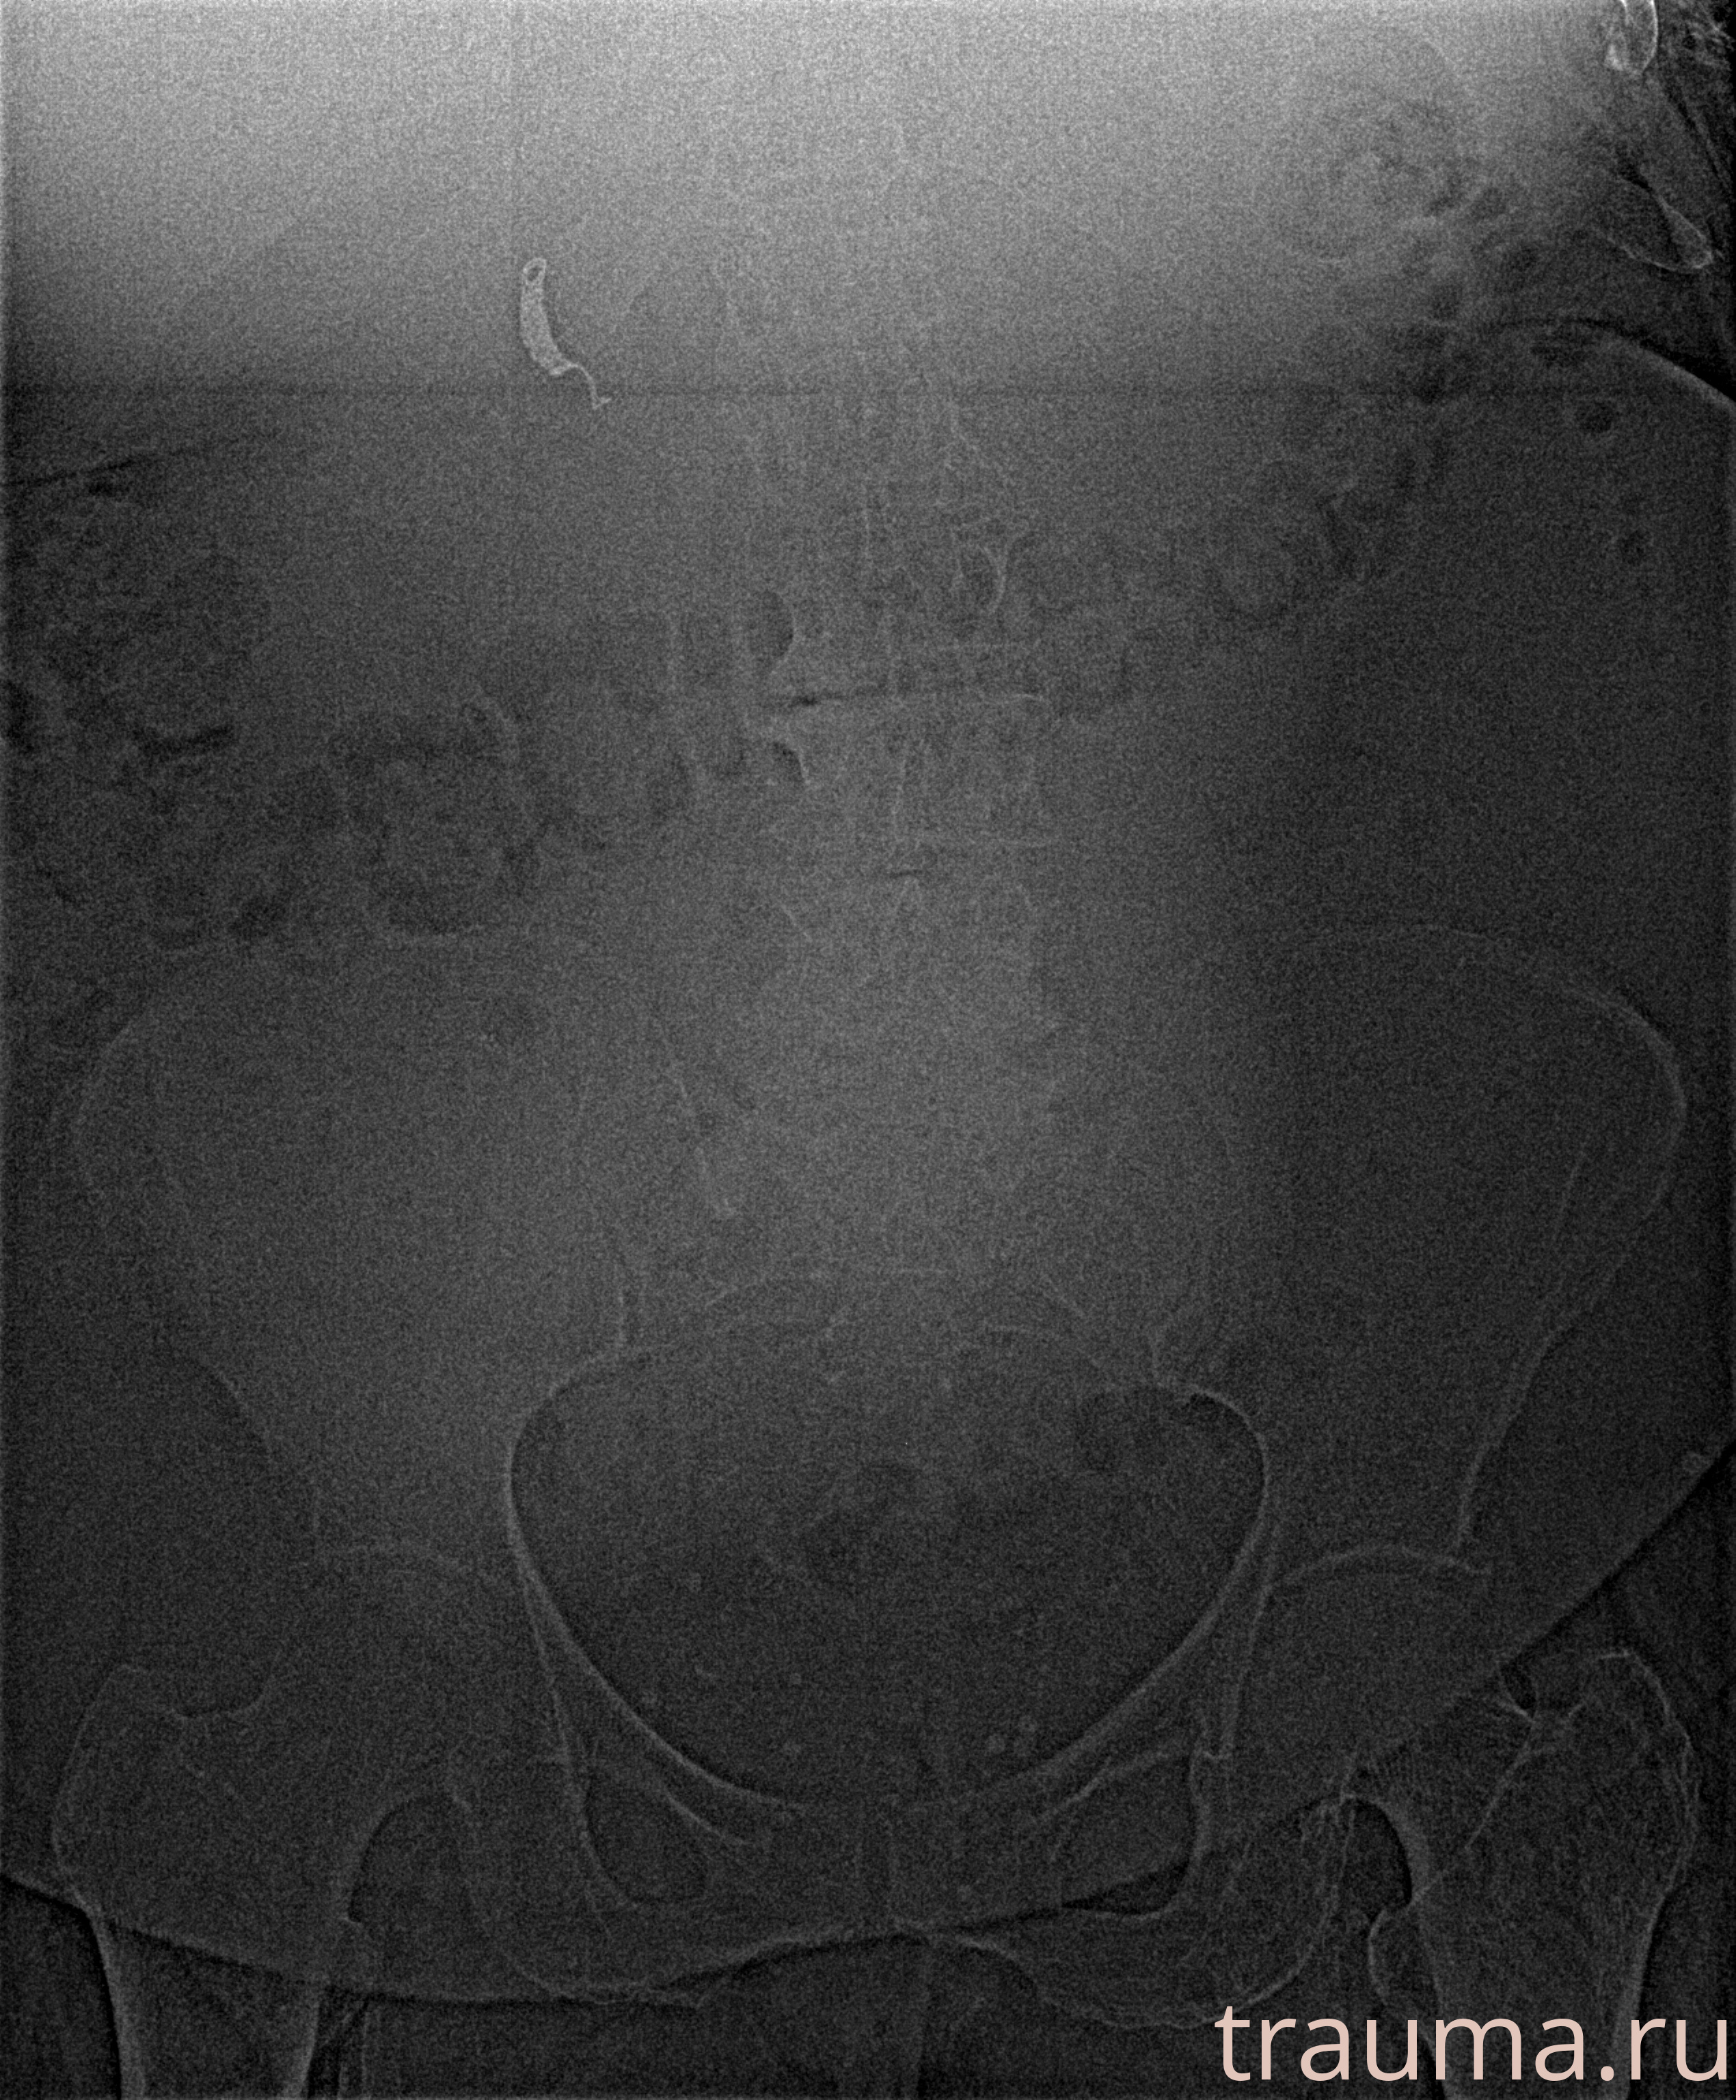

Рентгенограммы

Рентген на дому: по вашему адресу приезжает врач-рентгенолог, травматолог-ортопед с мобильным рентгеновским аппаратом, проводит диагностику травмы или заболевания, делает необходимые рентгенограммы, дает рекомендации по дальнейшему лечению. Получить качественные снимки в домашних условиях возможно благодаря уникальной методике, разработанной МосРентген Центром для института  Склифосовского